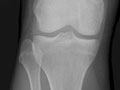

Extremity X-Ray

An extremity X-ray is a picture of your hand, wrist, arm, foot, ankle, knee, hip, or leg. It is done to see whether a bone has been fractured or a joint dislocated. It is also used to check for an injury or damage from conditions such as an infection, arthritis, bone growths (tumors), or other bone diseases, such as osteoporosis.

• Find changes in your bones caused by conditions such as an infection, arthritis, bone growths (tumors), osteoarthritis of the hip, osteoarthritis of the knee, or other bone diseases.